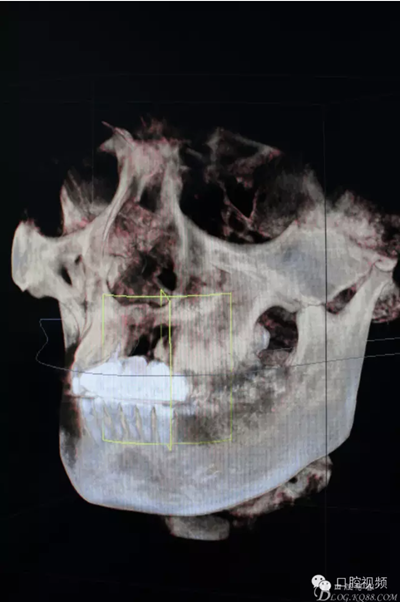

【原創(chuàng)博客】烤瓷橋下的悲劇-張東星